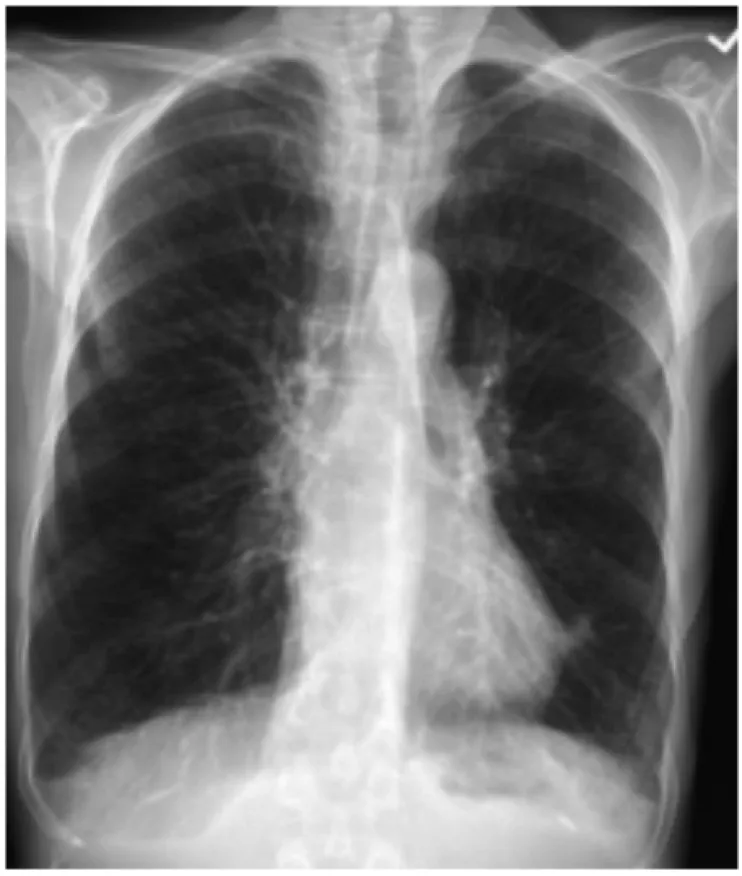

78세 남성이 숨이 차서 왔다. 환자는 3년 전부터 10분 정도 걸으면 숨이 차서 쉬었다 걸었다고 한다. 최근 5일 전부터 기침과 가래가 있었으며, 어제부터는 앉아 있어도 숨이 차다고 한다. 35갑년의 흡연력이 있다. 혈압 150/90mmHg, 맥박 110회/분, 호흡 25회/분, 체온 36.7'C, 산소포화도 92%로 측정되었다. 환자는 의식이 맑았으나, 청진 시 양측 하부 폐에서 호흡음이 감소되어 있었다. 가슴 X선 사진을 통해 확인한 결과는?

• 가슴 X선 사진 상 흉곽의 직경이 커지고 횡격막이 눌려 평평해진 과다팽창(hyperinflation) 소견을 보여 COPD를 의심할 수 있다.